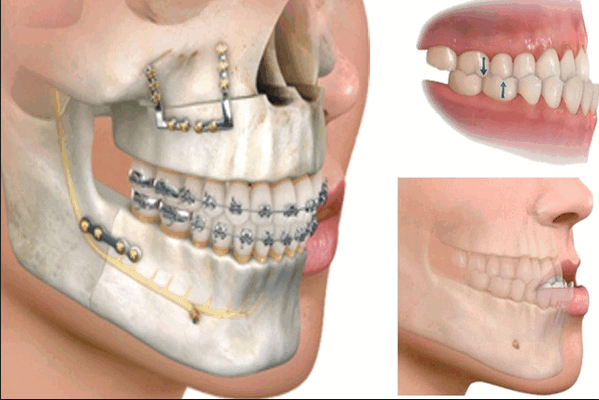

Хирургическое исправление зубочелюстных патологий называется остеотомией. Данный вид операций предполагает проведение различного рода манипуляций путем хирургического вмешательства в костную ткань: наращивание кости, изменение формы подбородка, удлинение либо укорачивание челюсти, удаление зубов и др. Все операции по исправлению аномалий прикуса проводятся строго по медицинским показаниям, поскольку любое хирургическое вмешательство является большим стрессом для всего организма и требует длительного восстановления.

Данная операция проводится путем хирургических надрезов кости, которая расположена позади жевательной группы зубов. Таким образом, челюсть устанавливается в правильное положение, при этом костные фрагменты соединяют с помощью пластин, изготовленных из титана до того момента, пока не вырастет костная ткань.

Остеотомия на верхней челюсти

В этом случае надрезы проводят над зубами, чуть ниже края глазниц. При этом челюстно-лицевой хирург может беспрепятственно сдвигать кость , одновременно перемещая небо и верхние зубы челюсти. Для закрепления правильно положения костные фрагменты скрепляют при помощи винтов, шин либо титановых пластин. Подробнее тут.

Гениопластика

Ментопластика подбородка (исправление формы подбородка). Во время операции отсекается часть костной ткани, которая затем устанавливается в правильном положении.

Сегментарная остеотомия

При данном хирургическом вмешательстве челюстная кость рассекается на сегменты, которые затем сопоставляют в нужном положении вместе с зубами и фиксируются.